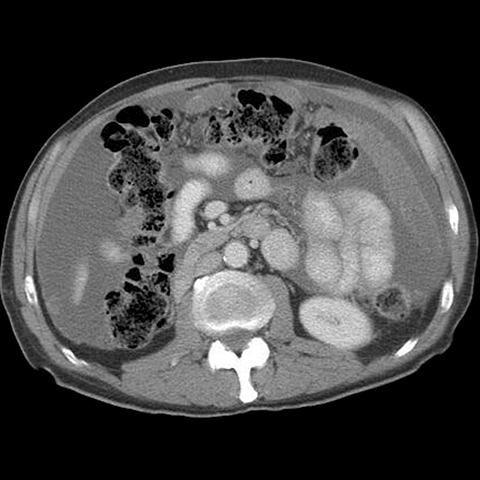

77 year-old woman with a history of ovarian cancer presents with increasing abdominal girth. [6 of 6]